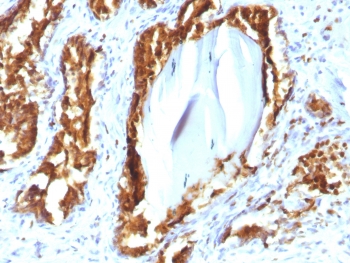

PSAP Antibody Recombinant Mouse MAb rACPP/1338 immunohistochemistry analysis of Prostatic acid phosphatase / ACP3 in human prostate carcinoma tissue. FFPE human prostate carcinoma tissue was stained with PSAP Antibody Recombinant Mouse MAb rACPP/1338 following heat induced epitope retrieval by boiling tissue sections in 10mM citrate buffer (pH 6) for 10-20 minutes and cooling at room temperature prior to staining. HRP-DAB brown chromogenic signal highlights strong cytoplasmic and membranous staining of prostate tumor epithelial cells forming glandular carcinoma structures, consistent with the known localization of Prostatic acid phosphatase (ACP3 / PAP) in prostate-derived epithelial cells. Detection of PSAP expression by immunohistochemistry is widely used in prostate cancer research to identify prostate epithelial lineage and evaluate PAP expression in prostate carcinoma tissues.